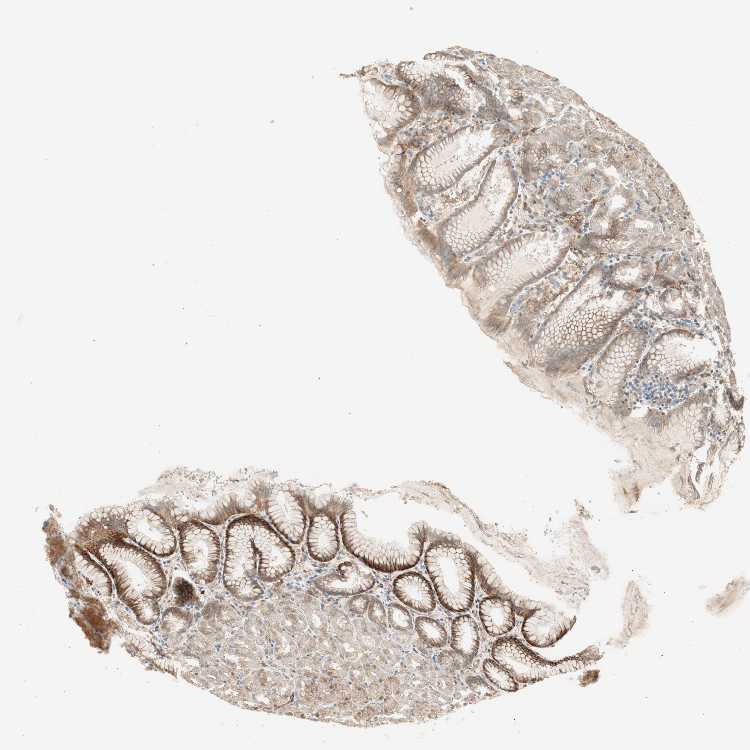

STOMACH 2 - Antibody stainingi

Antibody staining in the annotated cell types in the current human tissue is reported as not detected, low, medium, or high, based on conventional immunohistochemistry profiling in selected tissues. This score is based on the combination of the staining intensity and fraction of stained cells.

Each image is clickable and will lead to virtual microscopy that enables deeper exploration of all samples and also displays staining intensity scores, fraction scores and subcellular localization as well as patient and tissue information for each sample.

Antibody HPA003750

Glandular cells High